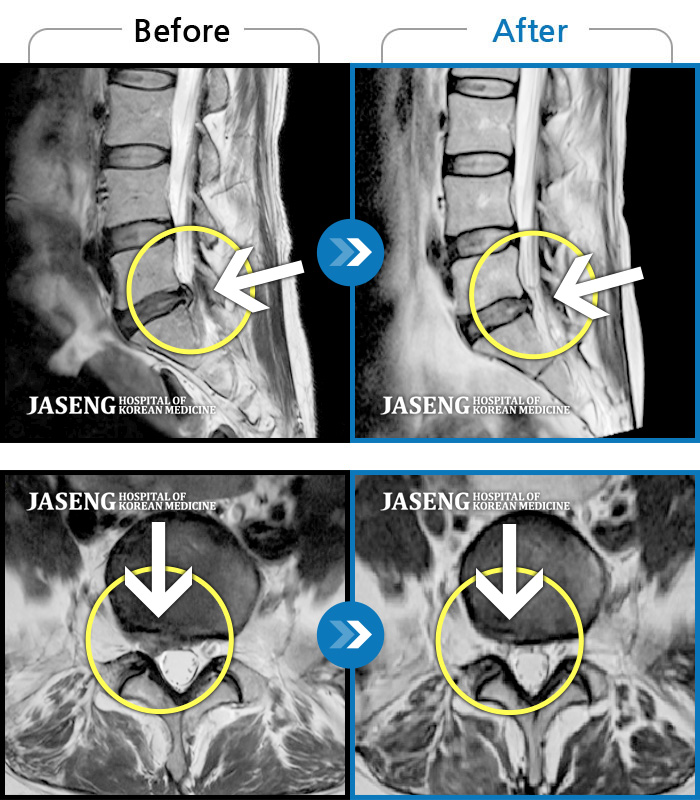

ȯںп  Ǹ   ǿ ԿǾ, ο  ġ  ۿ     Ƿ   ġḦ Ͻñ ٶϴ.